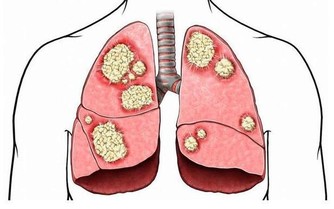

喝酒傷肝是大家都知道的道理,但如果你認為這裡說的傷肝是脂肪肝就大錯特錯了。酒精的成分是乙醇,乙醇需要靠肝臟進行代謝,而肝臟有許多工作要做,分解酒精只是他其中一項任務,所以每次都只能負荷一定含量的酒精,如果持續飲酒過量,不管是一次喝或是每天持續喝,都會讓肝臟持續超量工作,形成脂肪肝或是酒精性肝炎、肝硬化,甚至肝癌。